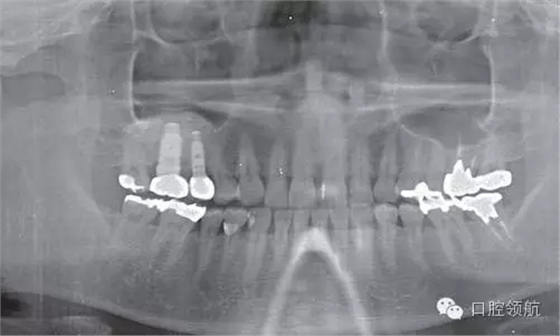

術(shù)后8個月未見異常(圖8),并完成( 左上第五顆牙) 的上部修復(fù)(圖9)。

圖8 術(shù)后8個月的牙片。兩顆種植體愈合良好。

圖9 術(shù)后8個月戴入上部修復(fù)后的曲面斷層片。

術(shù)后經(jīng)過1年多,目前無任何異常并行使功能。像這個病例,在上頜竇提升術(shù)后,隨著時間推移,生成骨逐漸消失的情況下,必須考慮再度行上頜竇提升術(shù)的必要性。但是否保留種植體判斷起來比較困難。